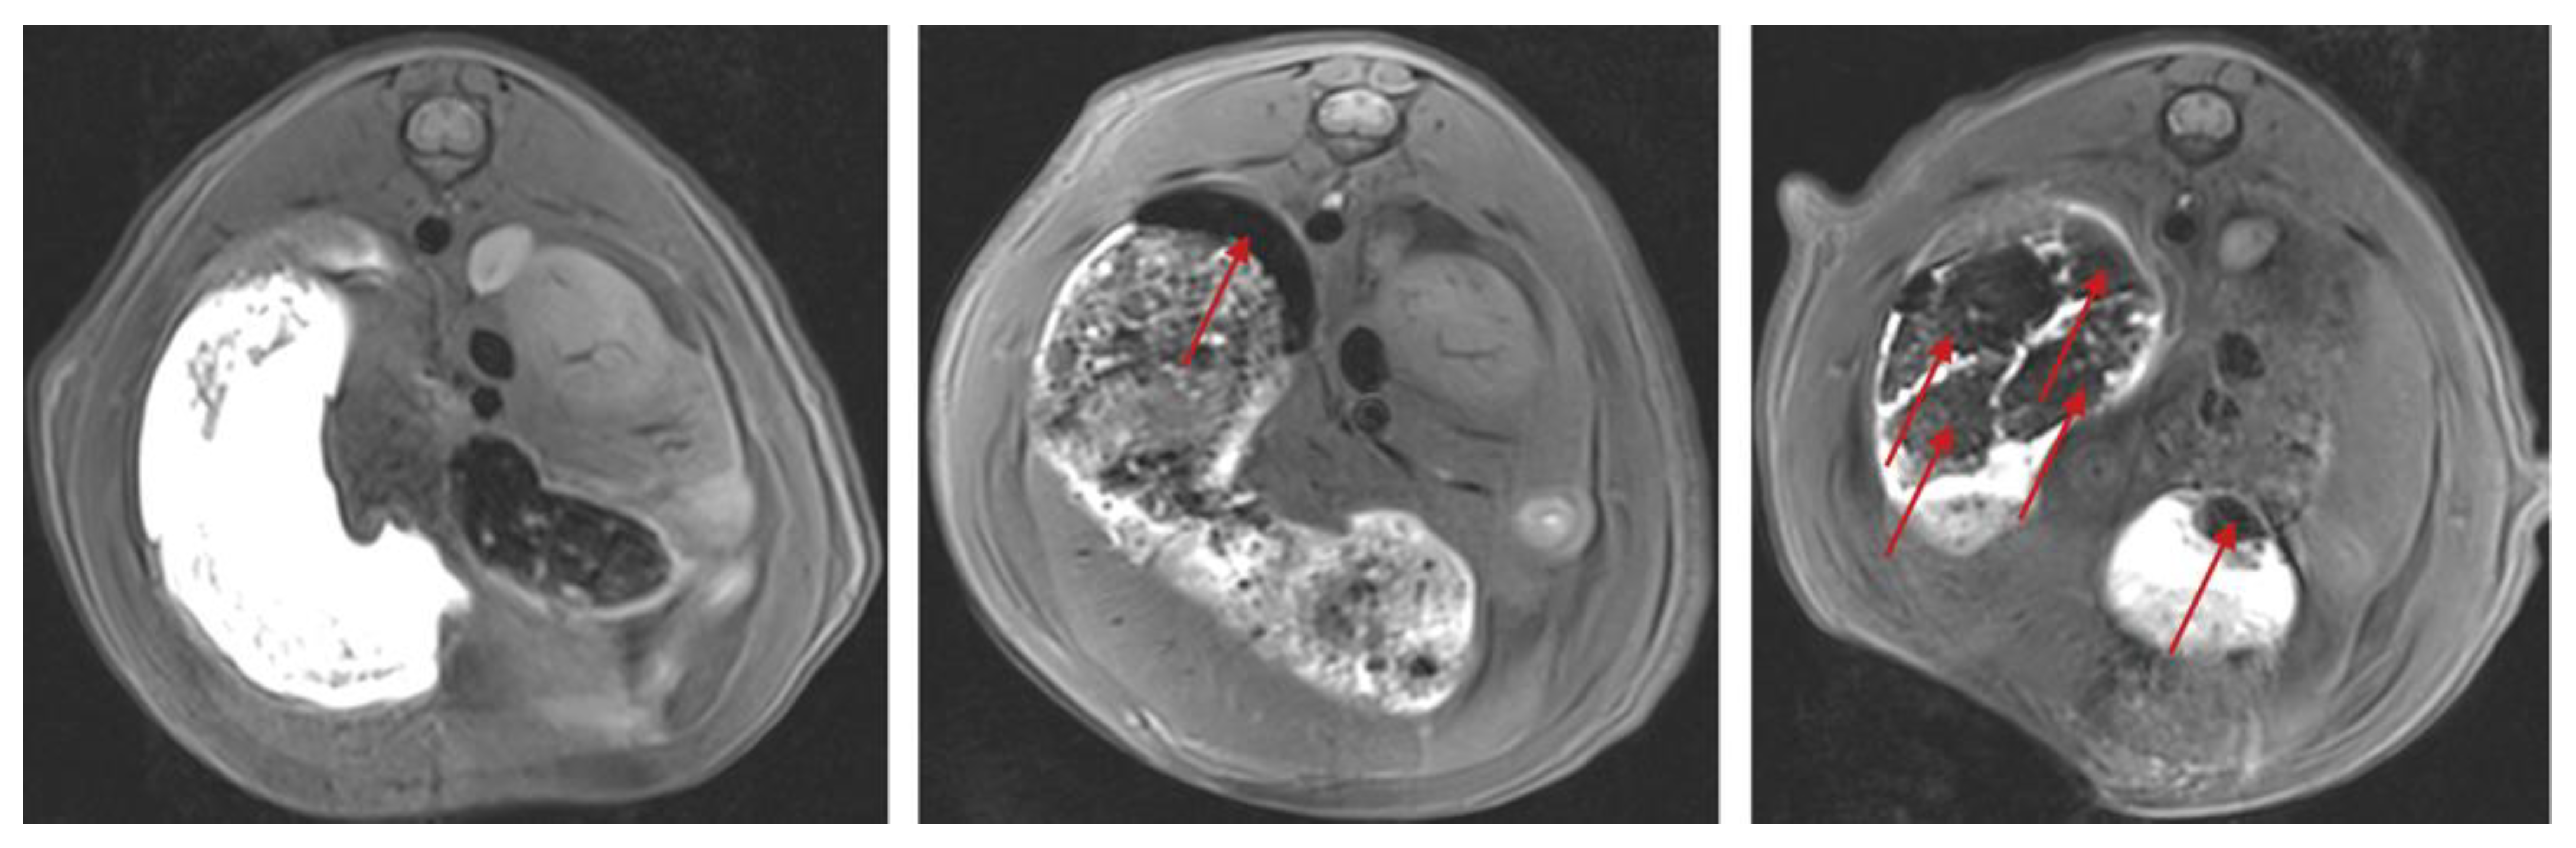

1. Introduction

2. Materials and Methods

3.1. Dose Finding Study

3.2. Main Study